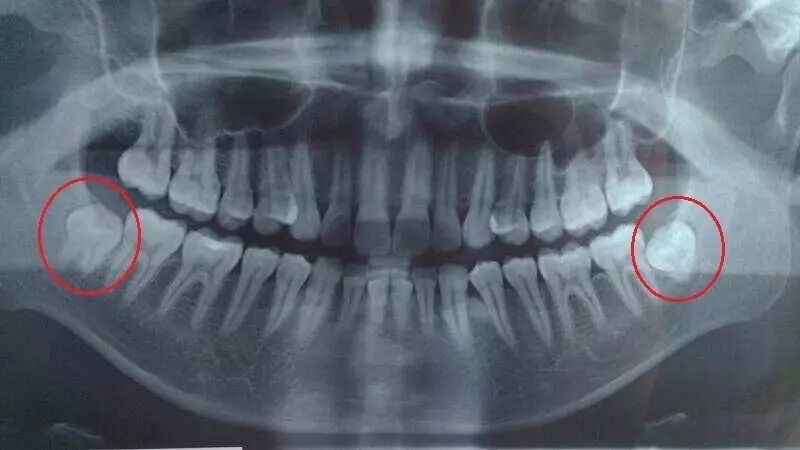

多出的智齿由于萌出空间不足就会出现歪着长,斜着长,横着长甚至倒着长,顶着邻近的臼齿长等情况。

各种长歪的智齿

○ 挤压邻牙

和相邻的恒牙挤着生长的智齿,易致恒牙不易清洁或出现牙齿部分被吸收的现象,造成患者出现牙痛或其它不适感。

这种情况下的智齿,患者不容易感受到,通过X光照射就能很清晰地看见。

○ 阻生智齿

阻生智齿通常都埋在牙槽骨里面,病人长了这种智齿不一定有感觉。

因而非常容易被忽略,但可通过拍X光片诊断出。

如果感觉到痛,或是通过口腔检查和X光片诊断有病灶发生,那就需要拔除。